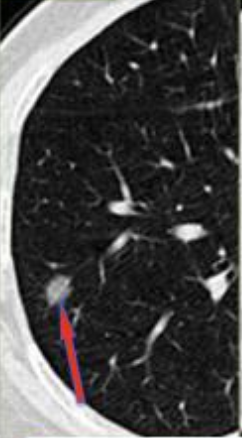

周二早晨,我的主人早早来到了吉林省肿瘤医院,直接给我来了个CT检查, CT报告提示右肺可见一亚实性结节,直径约9mm,实性成分较3个月前增多,边缘毛糙,可见血管征,建议MDT会诊。

肺结节临床恶性评估要点,主要包括结节外观评估和内部特征两方面:1.外观评估主要包括结节的大小、形态和边缘:一般来说,结节越大,形态不规则,边缘分叶或毛刺(类似于小刺猬)、血管越多(肿瘤生长需要营养供应),恶性概率越大;2.内部特征,如密度不均匀,实性成分超过50%和/或结节包埋支气管且局部管壁增厚,常提示结节恶性可能性大。